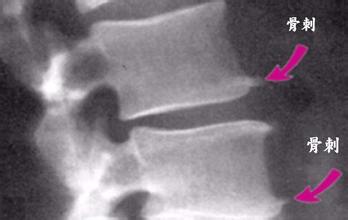

风湿关节炎是一种常见的急性或者慢性结缔组织炎症,是风湿热的一种表现,常见症状是关节轻度或者中度发热,关节多为膝,踝、肩、肘,腕等大关节,常常由一个关节转移到另一个关节,患…「查看详情」

济南中德骨科医院接诊一位患者,全身的膝、脚踝、肩、肘关节等处都可见红肿的情况,询问病史才知道,原来患者有喜欢睡地板的习惯,风湿性关节炎的典型表现是轻度或中度发热,游走性多…「查看详情」

李先生去年1月份晚上出去受凉膝盖开始疼,一直没拿当回事,后来越来越厉害有摩擦音,到了现在双膝关节疼痛而且摩擦音很大,遇冷后双肘关节发麻,检查后确诊为风湿性关节炎。风湿性关…「查看详情」

类风湿关节炎的病因相对于其他的骨科疾病来说较为复杂,这种病是有多种因素共同作用的结果,哪些原因会导致类风湿关节炎呢?…「查看详情」